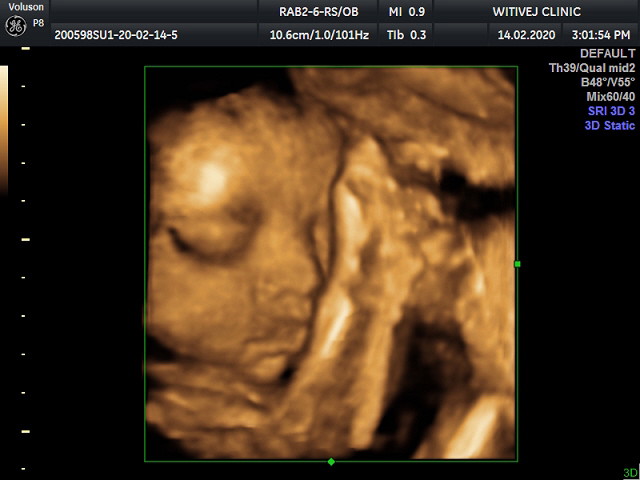

หน้าตาพ่อมาเต็มๆ ใครได้พ่อมาเต็มๆบ้าง นู๋เป็นผู้หญิงค่ะ

จมูกโด่งจริงๆ???

ซาวด์แบบนี้เรียกซาวด์อะไรคะ หมอเป็นคนซาวด์ให้เอง หรือเราขอหมอซาวด์คะ

อันนี้ 3 มิติค่ะ เราฝากรพ.เอกชน ซาวด์ทุกเดือนค่ะ